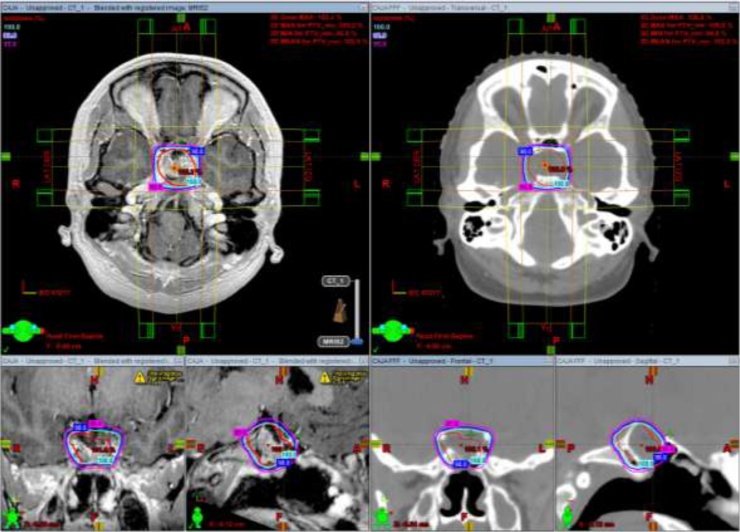

Fig. 1.

Isodose curves of D100% (cyan), D98% (blue) and D95% (magenta) with C3D (left) and C3D FFF (right) with axial, coronal, and sagittal views of MRI and CT, respectively. Abbreviations: C3D, conformal 3D radiotherapy; C3D FFF, conformal 3D radiotherapy flattening filter-free; MRI, magnetic resonance imaging; CT, computed tomography. (For interpretation of the references to colour in this figure legend, the reader is referred to the web version of this article).